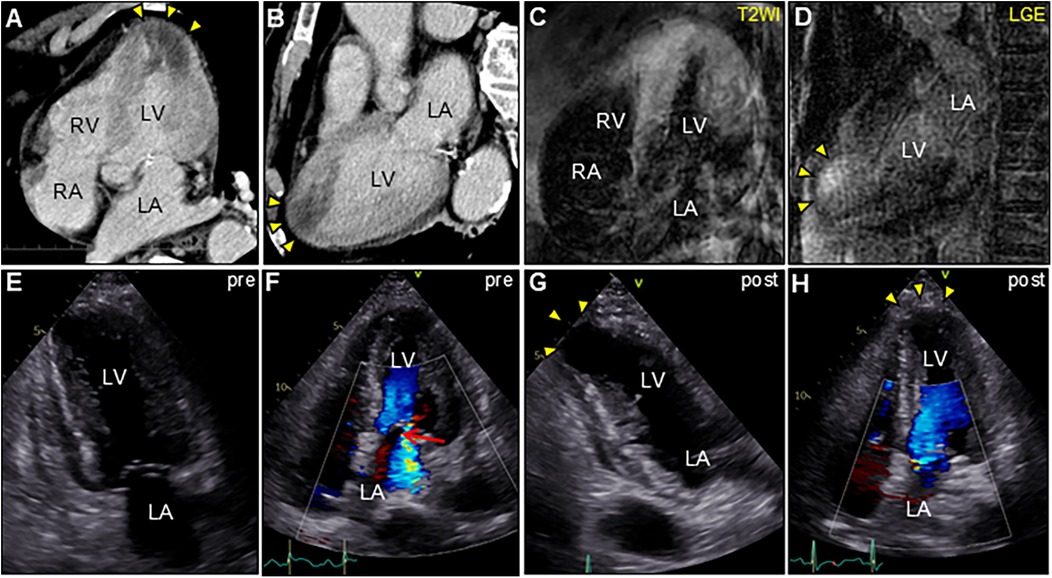

An 85-year-old man with high-grade fever, nausea, fatigue, and urinary disturbance was admitted to our hospital. The patient had a history of hypertension and benign prostatic hyperplasia, but no history of autoimmune gastrointestinal disorders. His vital signs were as follows: blood pressure, 160/102 mmHg; heart rate, 99 beats/min; and body temperature, 38.2°C. A physical examination revealed a distended abdomen. Abdominal computed tomography (CT) revealed an enlarged prostate gland with a distended bladder wall and bilateral hydronephrosis, suggesting a urinary obstruction. Empirical antimicrobial treatment with intravenous ceftriaxone was initiated for suspected urinary tract infection. On day 2, the patient became agitated, disoriented, and unable to follow instructions. Neurological examination revealed left hemiparesis and profound bilateral hearing loss. Electrocardiography showed atrial fibrillation with tachycardia and ST-segment elevation in the precordial leads (Figure 1A). Brain magnetic resonance imaging (MRI) revealed multiple cerebral emboli and bilateral acute otitis media (AOM) (Figures 1B–D). Laboratory tests revealed a white blood cell count of 6,200/μl without eosinophilia and an elevated C-reactive protein (CRP) level of 7.47 mg/dl (normal: <0.3 mg/dl). Additionally, elevated levels of serum cardiac troponin I (cTnI; 11,023 pg/ml, normal: <26.2 pg/ml) and N-terminal pro-brain natriuretic peptide (NT-proBNP; 885 pg/ml, normal: <125 pg/ml) were observed. Coronary angiography and left ventriculography were unremarkable (Figure 1E). Echocardiography revealed left ventricular (LV) hypertrophy, preserved LV contraction, and mild pericardial effusion. Enhanced CT indicated acute myocardial edema of the LV apex involving the anterolateral pupillary muscle (Figures 2A,B). Cardiac MRI established acute myocarditis (Figures 2C,D). The repeated urine and blood cultures remained sterile. The fever and inflammatory response without leukocytosis raised the suspicion of acute viral myocarditis with concomitant cardiogenic emboli. The patient underwent close telemetric monitoring with intravenous heparin infusion, followed by oral anticoagulant and anti-heart failure treatment. Furthermore, acetaminophen was administered for AOM. On day 6, the patient was transferred to the intensive care unit (ICU) due to cardiogenic shock, requiring intubation and catecholamine support. Follow-up electrocardiography revealed pathological Q waves with complete ST-segment resolution. Follow-up echocardiography revealed severe diffuse global hypokinesis with severe mitral regurgitation (Figures 2E,F; Supplementary Videos S1 and S2). Follow-up laboratory examinations revealed a greater increase in serum cTnI (18,946 pg/ml), NT-proBNP (35,000 pg/ml), and CRP (10.08 mg/dl) levels. Note the transient increase in the circulating absolute eosinophilic count to 542 cells/μl (Supplementary Figure S1). Repeated left ventriculography confirmed reduced global systolic function with an ejection fraction of 35%, followed by the insertion of an intra-aortic balloon pump (IABP). Subsequent endomyocardial biopsy (EMB) revealed numerous eosinophilic infiltrations admixed with CD3+/CD4 + helper T lymphocytes, macrophages, and adjacent cardiomyocyte injury (Figures 3A, B, D–F). Immunostaining for major basic proteins demonstrated extensive staining, predominantly eosinophils in the endocardium (Figure 3C), with macrophage polarization toward the M2 phenotype (Figures 3G,H). These findings confirmed a definitive diagnosis of acute eosinophilic myocarditis (AEM), which was treated with intravenous methylprednisolone (1 g/day for 3 days), followed by oral prednisolone (1 mg/kg/day) with gradual dose tapering. Thereafter, the patient remained hemodynamically stable. The IABP was weaned off on day 12, and the patient was transferred from the ICU to the general ward.

Figure 2. Enhanced computed tomography (CT) and cardiac magnetic resonance imaging (CMR) (A,C, apical four-chamber view; B,D, long-axis view). CT showing low-attenuation areas of the left ventricular apex (arrowheads). T2-weighted image (T2WI) showing diffuse myocardial edema. Late gadolinium enhancement (LGE) images showing the same region as that of CT (arrowheads). Serial transthoracic echocardiography (TTE). (E,G, apical two-chamber view; and F,H, apical four-chamber view). (E,F) TTE on day 6 after admission showing severe global left ventricular systolic dysfunction with increased left ventricular wall thickness (LVWT) accompanied by severe mitral regurgitation (arrow) in color Doppler mode [LVWT, 14 mm; and ejection fraction (EF), 40%]. (G,H) Follow-up TTE 2 weeks after corticosteroid treatment showing considerable improvement in left ventricular function and mitral regurgitation (LVWT, 12 mm; and EF, 57%). Note the left ventricular apical aneurysmal formation (arrowheads). LA, left atrium; LV, left ventricle; RA, right atrium; RV, right ventricle.